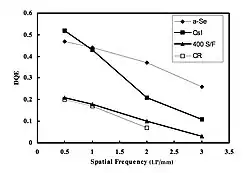

The DQE combines the effects on modulation, spatial frequency and noise of an image receptor and can be used to compare different receptors in a more general manner than the MTF alone - see Figure 6.17. The parameter relates the signal to noise ratio (SNR) of images displayed by the imaging system, SNRout, to the SNR of the incident X-ray intensity pattern, SNRin, i.e.

where the DQE is defined as a function of spatial frequency. The imaging performance of different image receptors receptors is illustrated in Figure 6.18. Note that a perfect image receptor would have a DQE of 1.0 at all spatial frequencies. In the cases illustrated, note that the DQE performance of CR is similar to that of a traditional regular screen/film combination. Note also that the digital technologies illustrated show substantially superior DQE at all spatial frequencies, heralding potential dose reductions relative to those necessary with traditional and CR image receptors. In addition, the DQE of indirect image receptors is about 10-15% greater than XII-video technology.